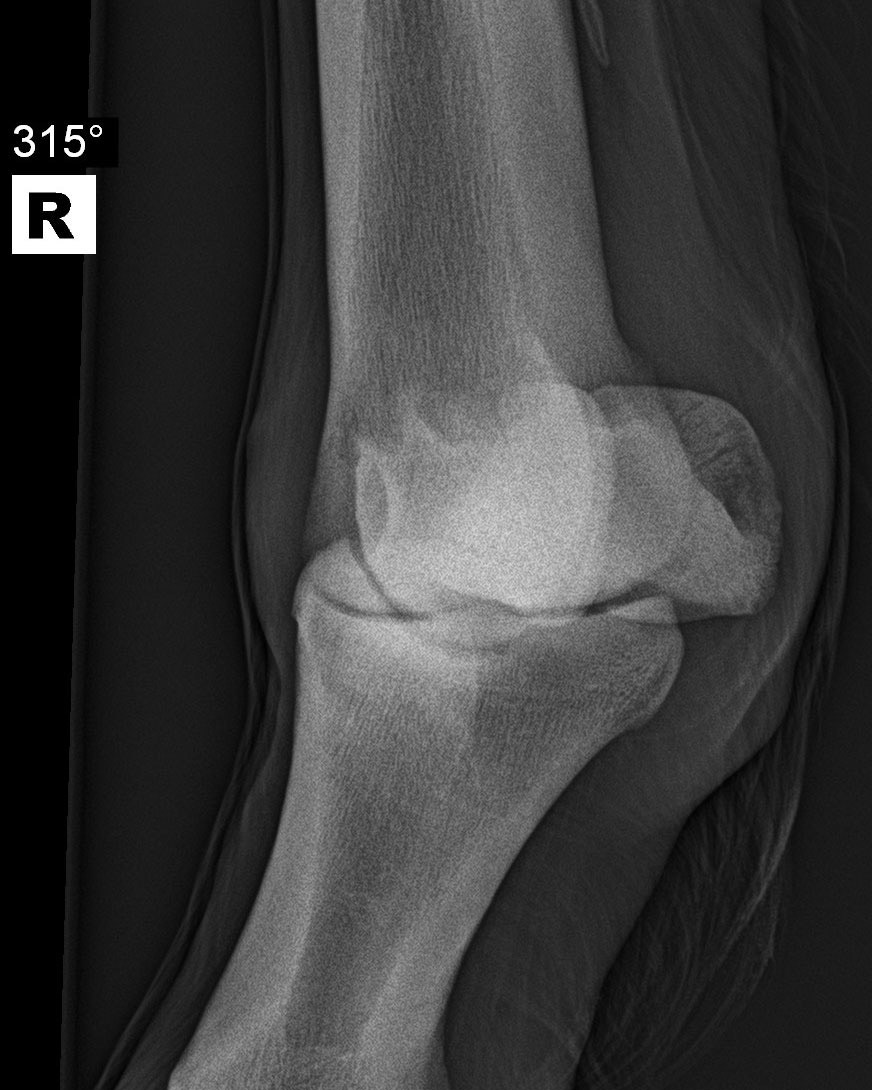

Fesselgelenk - Schrägaufnahme